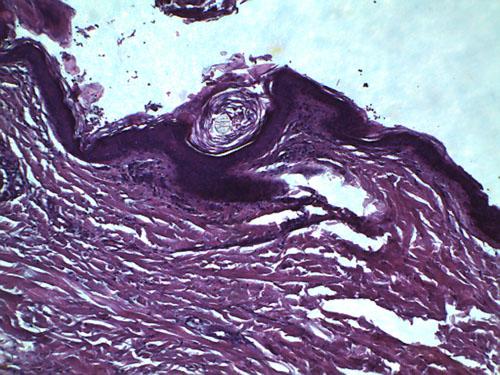

L’examen histopathologique de biopsies cutanées révèle une hyperkératose orthokératosique de la surface épidermique et des follicules pileux, ainsi qu’une mélanose dermique (photo 9).

Photo 9 : Observation microscopique (x400) d’une biopsie cutanée:

noter l’hyperkératose orthokératosique et la mélanose.